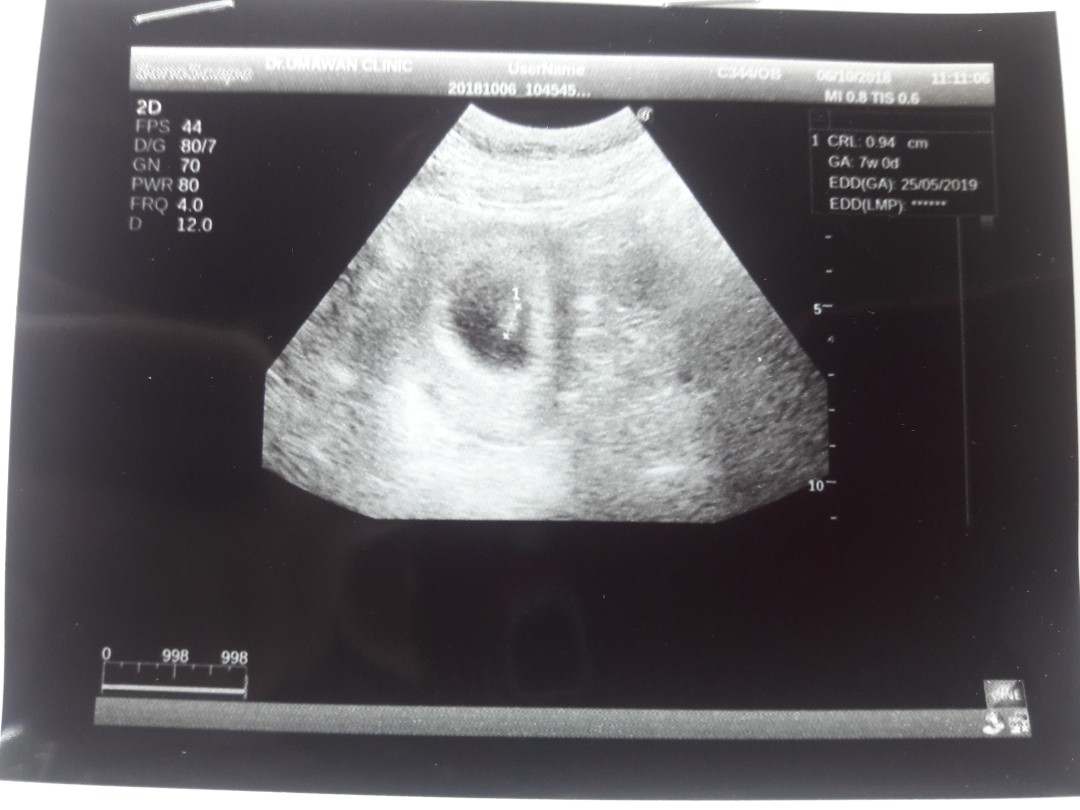

ตอน7วีคกับ2วันค่ะ ตอนนี้15วีคแล้ว💗

ภาพแรกเห็นแต่ไข่แดง กับหัวใจกระพริบจ้า